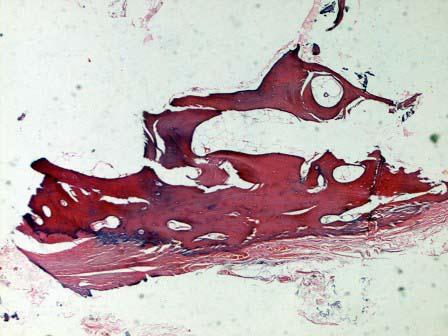

问题 患者,女,18岁,额头一无痛骨性肿块,大小2cm×1cm×1cm,出于美容的角度考虑予以切除,病检如图1、2所示,主要由成熟的骨质组成,但失去正常骨质的结构和排列方向。正确的病理诊断是 ( )

选项 A.软骨瘤 B.骨样骨瘤 C.骨瘤 D.骨软骨瘤 E.骨囊肿

答案 C